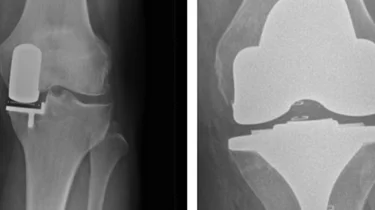

Ortopædkirurgi Lars Blønd har for nyligt udviklet en ny og vellykket operationsteknik til behandling af Artroscopisk Trokleoplastik, der udføres med en kikkertoperation.